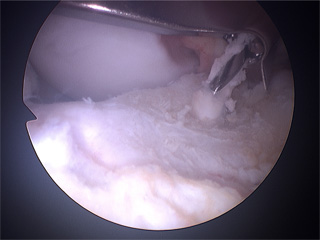

Die Kniearthroskopie ist eine chirurgische Technik, die einen Einblick in das Innere des Knies mit seinen kleinen Gelenkstrukturen ermöglicht, ohne einen größeren Eingriff vornehmen zu müssen. Es werden über zwei kleine Hautschnitte mit weniger als 6mm Länge auf beiden Seiten der Patellarsehne Präzisionsinstrumentarium und eine Kameralinse (Optik) eingeführt. Über die Fiberglasoptik wird das Bild auf einem Monitor dargestellt, so dass gemeinsam mit dem wachen Patienten in Spinalanästhesie (Rückenmarks-Narkose) die inneren Strukturen gesehen und das Vorgehen verfolgt werden kann.

Bei der Durchführung jeglicher Kniearthroskopie sollte mit einer kompletten, systematischen Spiegelung des gesamten Kniegelenks begonnen werden, da Läsionen entdeckt werden können, die vorher bei bildgebenden Verfahren (MRT/CT/Röntgen) nicht gesehen worden sind.